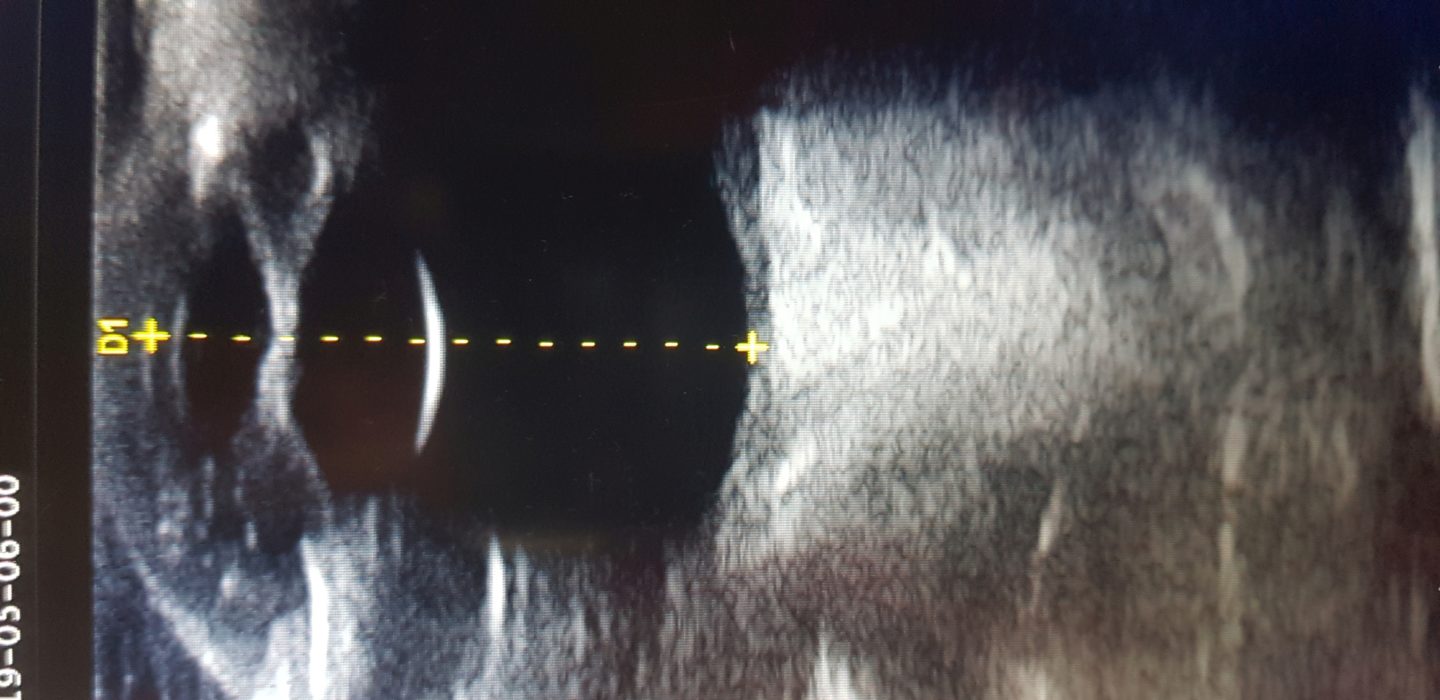

Da das rechte Auge mit der Untersuchungslampe nicht einsehbar war, wurde eine Ultraschalluntersuchung der Augen

durchgeführt. Dies ist gut am wachen Tier unter lokaler Betäubung der Hornhaut mit Augentropfen durchführbar. Im Ultraschall zeigte sich im rechten Auge eine hochgradige Schwellung der Iris, die sich wie ein Napfkuchen in die vordere Augenkammer vorwölbte (Abb. 4).